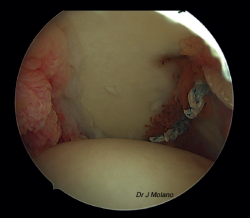

Figura 6. Visión artroscópica desde el portal posterior de la ligamentoplastia en hombro derecho previa a la reparación capsulolabral.